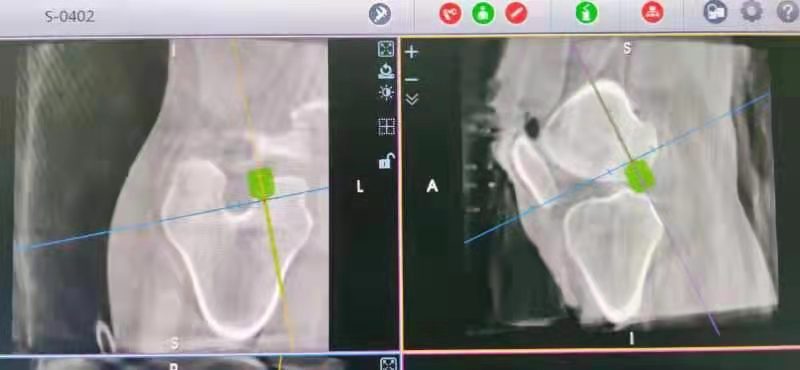

术中经3D-C臂扫描、数据采集、三维立体成像后,运用机器人系统软件规划出韧带重建过程中骨隧道导针的出入点和方向,经自动数据化处理,计算出符合医生要求的手术三维路径,发送指令使机械臂自动移动至最佳位置,建立精准的骨隧道,完成手术操作。本次手术用时约60分钟,术中出血约20ml。术后,患者膝关节活动度及稳定性获得了令人满意的效果。

3D-C臂扫描 数据采集

机器人辅助定位

机器人引导下钻骨隧道